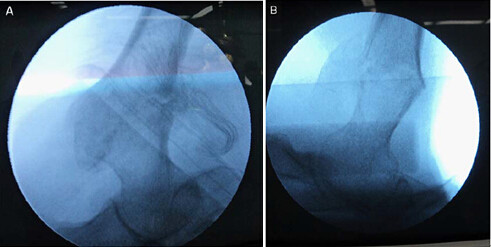

复位转子间骨折,并在正侧位下确认骨折复位成功;把屏幕固定在前后位下显示股骨头、颈和股骨近端,把量角器固定在 135°;量角器一只脚与股骨外侧皮质平行,另一只调整到股骨头和股骨颈的中心,在显示屏上作标记,帮助确认 DHS 固定位置。